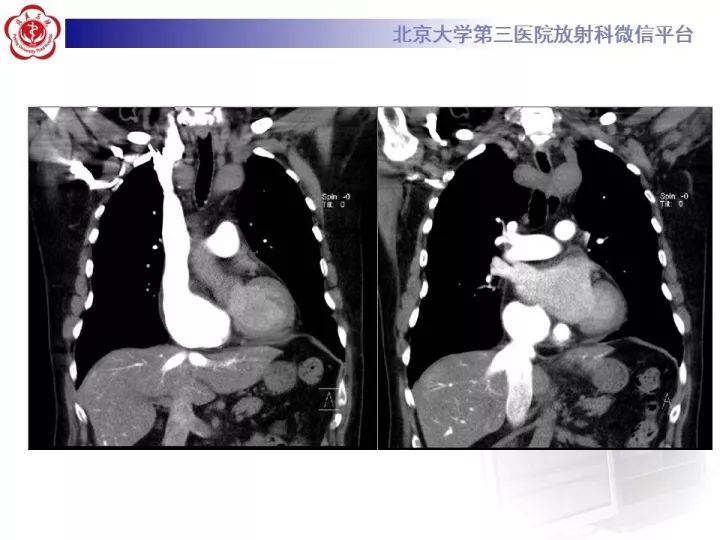

【病例】双主动脉弓畸形1例CT